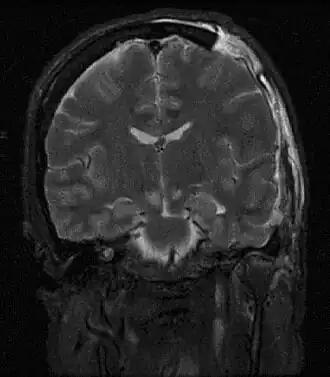

| Imagem por ressonância magnética de lesões causadas por uma hérnia cerebral | |

Hérnia cerebral é um efeito secundário potencialmente mortal de pressão intracraniana muito elevada, que ocorre quando parte do cérebro é pressionada contra as estruturas do crânio. O cérebro pode atravessar estas estruturas, como o falx cerebri, o tentorium cerebelli e até mesmo o foramen magnum (o orifício na base do cérebro pelo qual a espinal medula se liga ao cérebro).[1] Em muitos casos a hérnia cerebral apresenta-se com postura anormal, indicativa de lesões no cérebro.[2] Pode também ocorrer alteração do estado de consciência, com Escala de coma de Glasgow entre 3 e 5.[2] As pupilas podem-se apresentar dilatadas e não reagir à luz.[2]